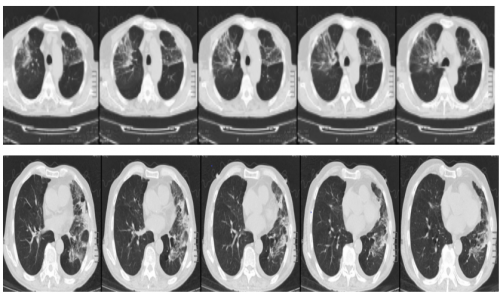

10.5日我院肺ct:肺ct显双肺片状、大片状高密度影,左侧可见少量胸腔积液。较自带肺ct明显进展。

转归:10.11日复查肺ct:与5日肺ct比较 炎症病灶有吸收,双侧胸腔积液增多(考虑与低蛋白血症有关)。10.12日出院后继续口服莫西沙星2周,甲泼尼龙片2周(逐渐减量)。症状明显好转,可下床活动。

10.11肺ct 如下

10.28 当地复查医院复查肺ct 如下 显示双肺多发斑片状影明显吸收好转。患者可正常活动。